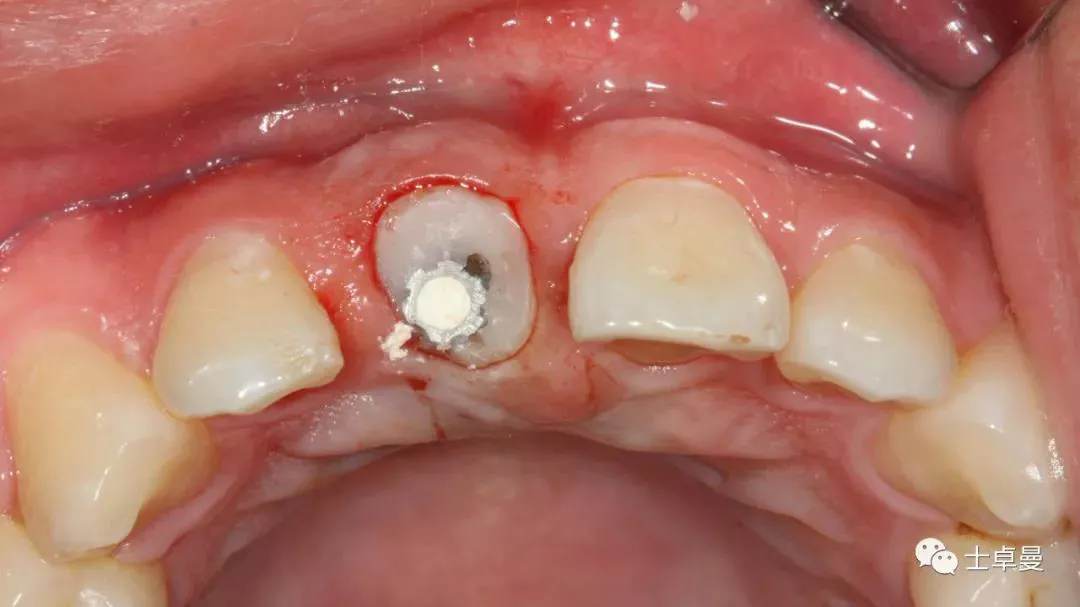

分根

拔出腭侧牙根

保留唇侧牙片

牙周探针探查牙片位置及松动度